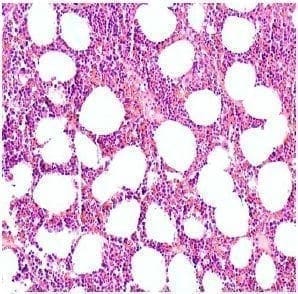

Figura 6. Se aprecia una proporción similar entre el componente adiposo y el hematopoyético del mielolipoma. Hematoxilina y eosina, 20X.

Figura 7 . El componente hematopoyético está conformado por elementos de todas las líneas celulares. Se destaca la presencia de un megacariocito en el centro de este campo. Hematoxilina y eosina, 40X.